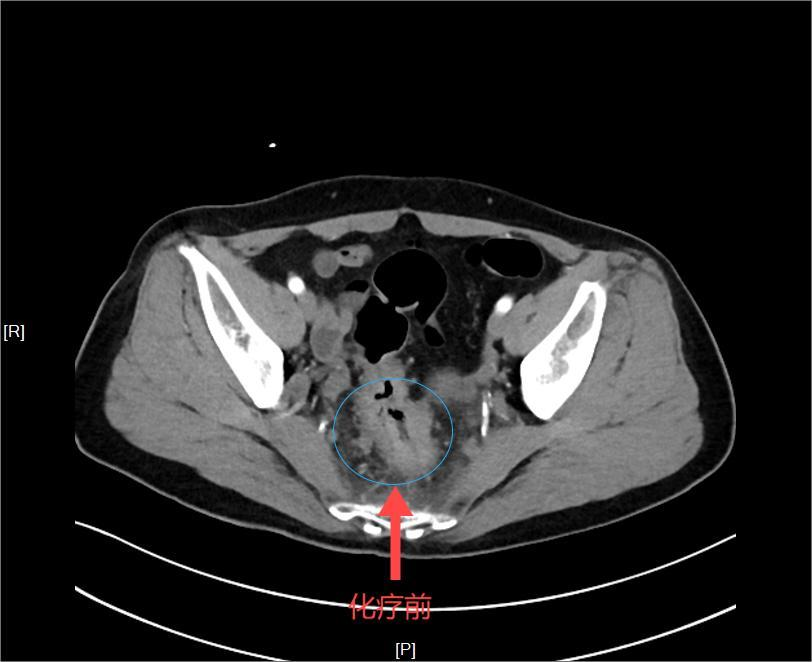

令人欣慰的是,经过四次两疗程的转化治疗后,刘阿姨明显感觉下腹部好像少了一样东西,身体轻松了好多。经过再次的增强CT评估,发现直肠肿瘤瘤体明显缩小,CT上几乎不可见,转移的淋巴结也明显缩小,显示出理想的治疗效果。

图片

▲化疗前